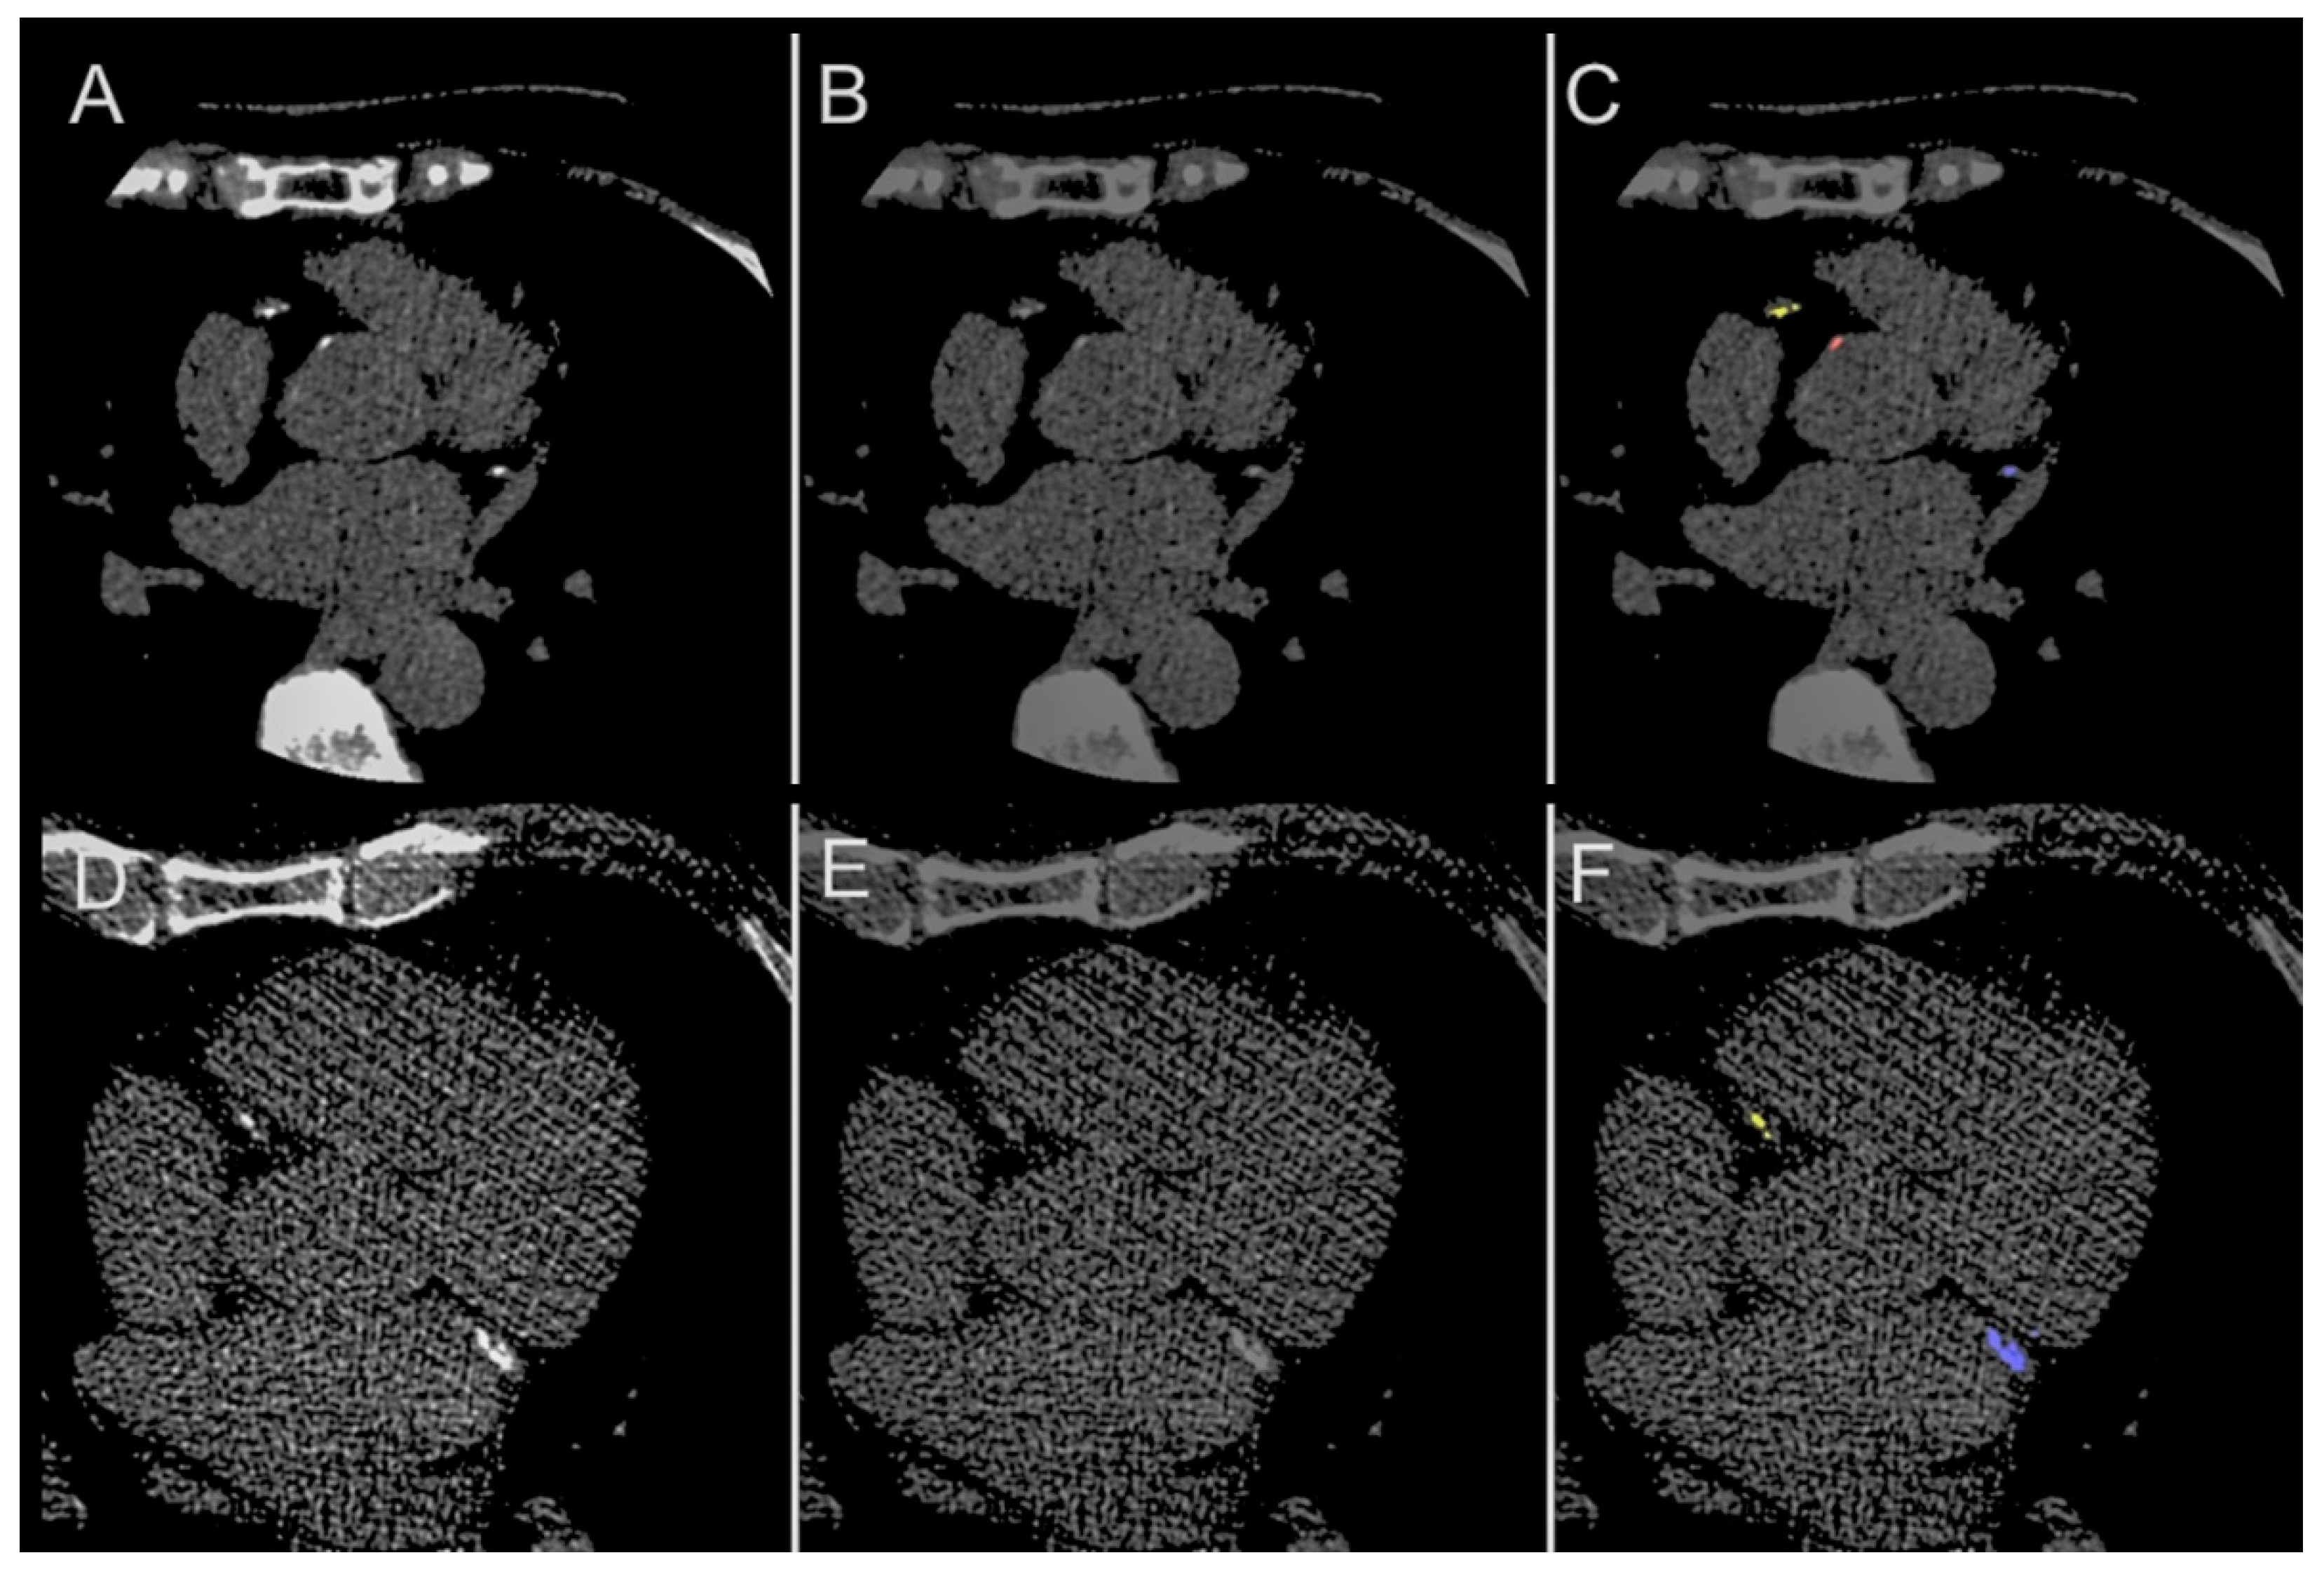

| Structure | Category | Dice Score | ||

|---|---|---|---|---|

| Median | Quartile (1st, 3rd) | p | ||

| Total coronary (LAD + RCA + LCx) | Overall | 0.952 | (0.921, 0.981) | - |

| LAD | Overall | 0.971 | (0.930, 1.000) | - |

| Male | 0.963 | (0.919, 1.000) | 0.058 | |

| Female | 0.988 | (0.968, 1.000) | ||

| Age < 65 years | 0.970 | (0.941, 0.999) | 0.980 | |

| Age ≥ 65 years | 0.975 | (0.911, 1.000) | ||

| RCA | Overall | 0.963 | (0.889, 0.991) | - |

| Male | 0.951 | (0.880, 1.000) | 0.633 | |

| Female | 0.977 | (0.923, 0.991) | ||

| Age < 65 years | 0.964 | (0.874, 0.999) | 0.875 | |

| Age ≥ 65 years | 0.959 | (0.899, 0.987) | ||

| LCx | Overall | 0.955 | (0.894, 1.000) | - |

| Male | 0.954 | (0.887, 1.000) | 0.388 | |

| Female | 0.958 | (0.942, 0.998) | ||

| Age < 65 years | 0.954 | (0.905, 0.999) | 0.897 | |

| Age ≥ 65 years | 0.955 | (0.887, 1.000) | ||

| Aortic | Overall | 0.832 | (0.759, 0.897) | |

| Male | 0.802 | (0.760, 0.905) | 0.996 | |

| Female | 0.834 | (0.764, 0.883) | ||

| Age < 65 years | 0.833 | (0.776, 0.933) | 0.204 | |

| Age ≥ 65 years | 0.793 | (0.756, 0.862) | ||